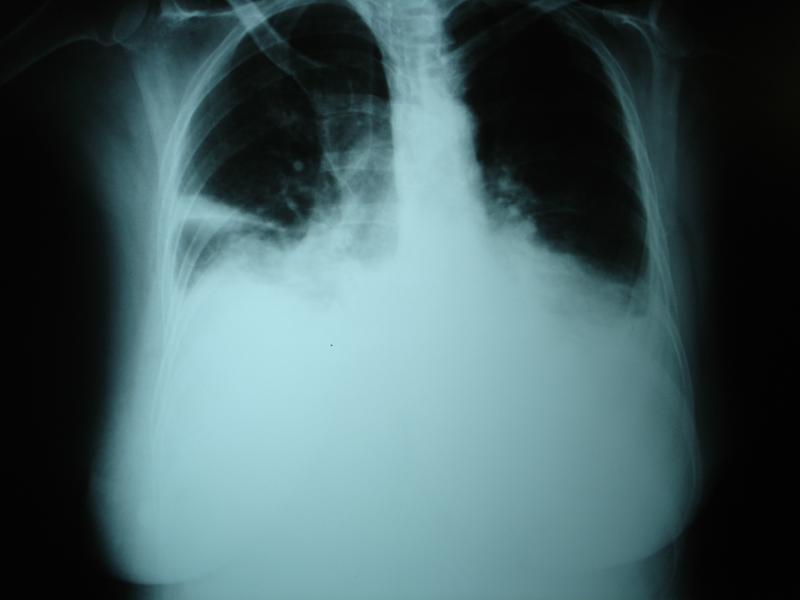

A total of 201 patients with PE who underwent thoracocentesis were included in this prospective review. The investigators assessed chest x-rays for laterality, followed by ultrasound (US) for echogenicity, pleural nodularity, thickening, and septations.

Based on Light’s criteria, PE was classified as either exudate or transudate and corroborated with albumin gradient. The investigators then developed a score that combines radiological and US features.